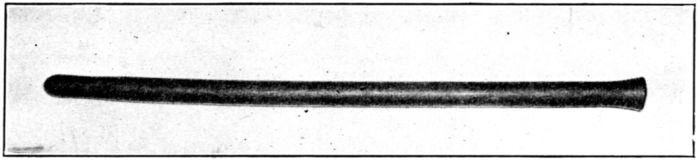

| 111. | Rubber bougie | 311 |